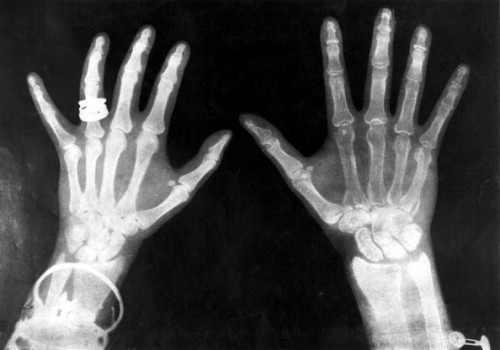

X-rays of the hands of King George V and Queen Mary, 1896